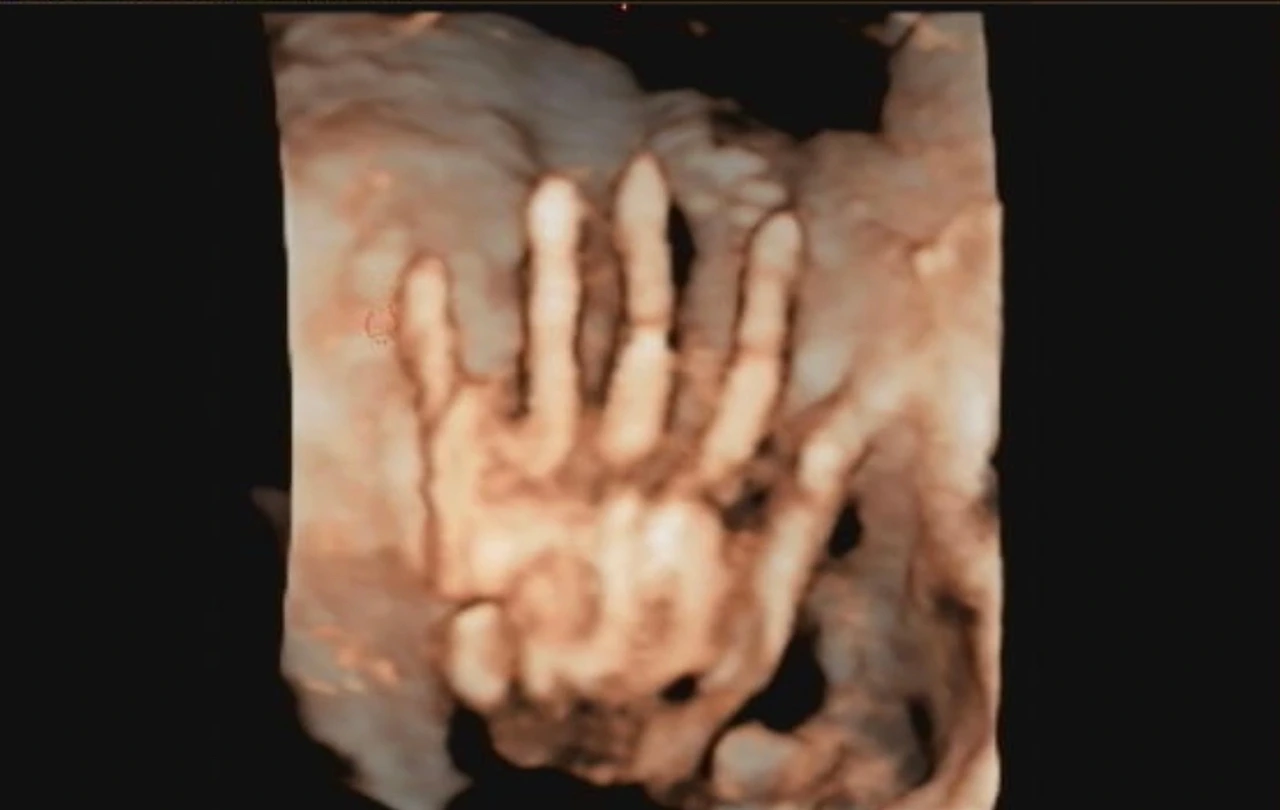

IMG_3698.jpeg 손가락 다섯 개에 감격하게 되는 순간

임신을 확인한 후 우리는 임신 어플을 깔았다. 마지막 생리 일자를 입력하면 자동으로 임신 주수를 계산해 매주 매달 푸시 알람을 보낸다. 임신 10주, 뇌세포가 대부분 완성되고 초기 입덧이 심할 시기입니다. 16주, 체중이 증가하고 태동을 느낄 수 있습니다. 27주, 아이 머리가 아래로 향하고 임신중독증에 주의하십시오, 등등. 태아의 발달 단계와 내 몸의 변화를 꾸준히 안내받았다. 2주에서 4주 간격으로 병원도 갔다. 초음파 화면으로 검은 점 같던 아기집에 흰 완두콩 같은 존재가 보이더니 인간의 형태를 갖추기 시작했다. 머리와 몸통에 팔다리가 보이고 심장이 뛰었다. 입체초음파를 찍던 날 선명한 눈 코 입에 우리는 감격했다.